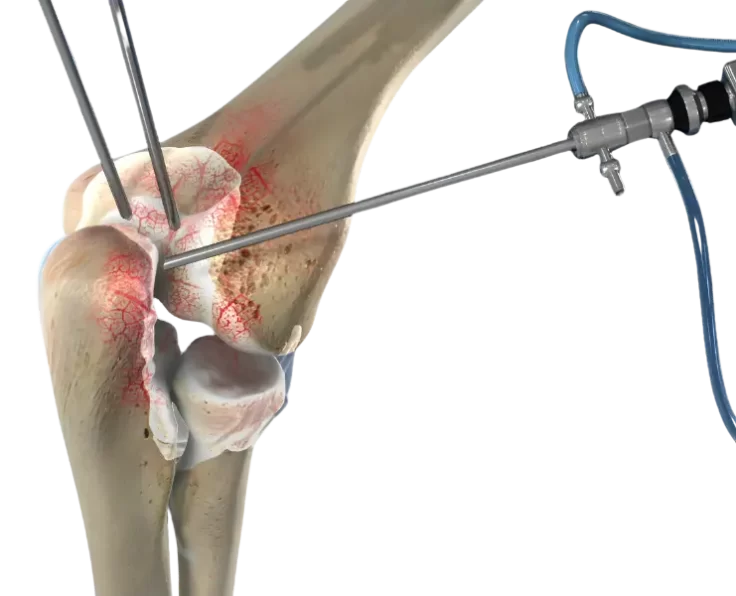

OATS for Elbow and Shoulder

The OATS procedure, which stands for osteoarticular transfer system, is a surgical treatment for focal cartilage defects and the type of procedure is called a…